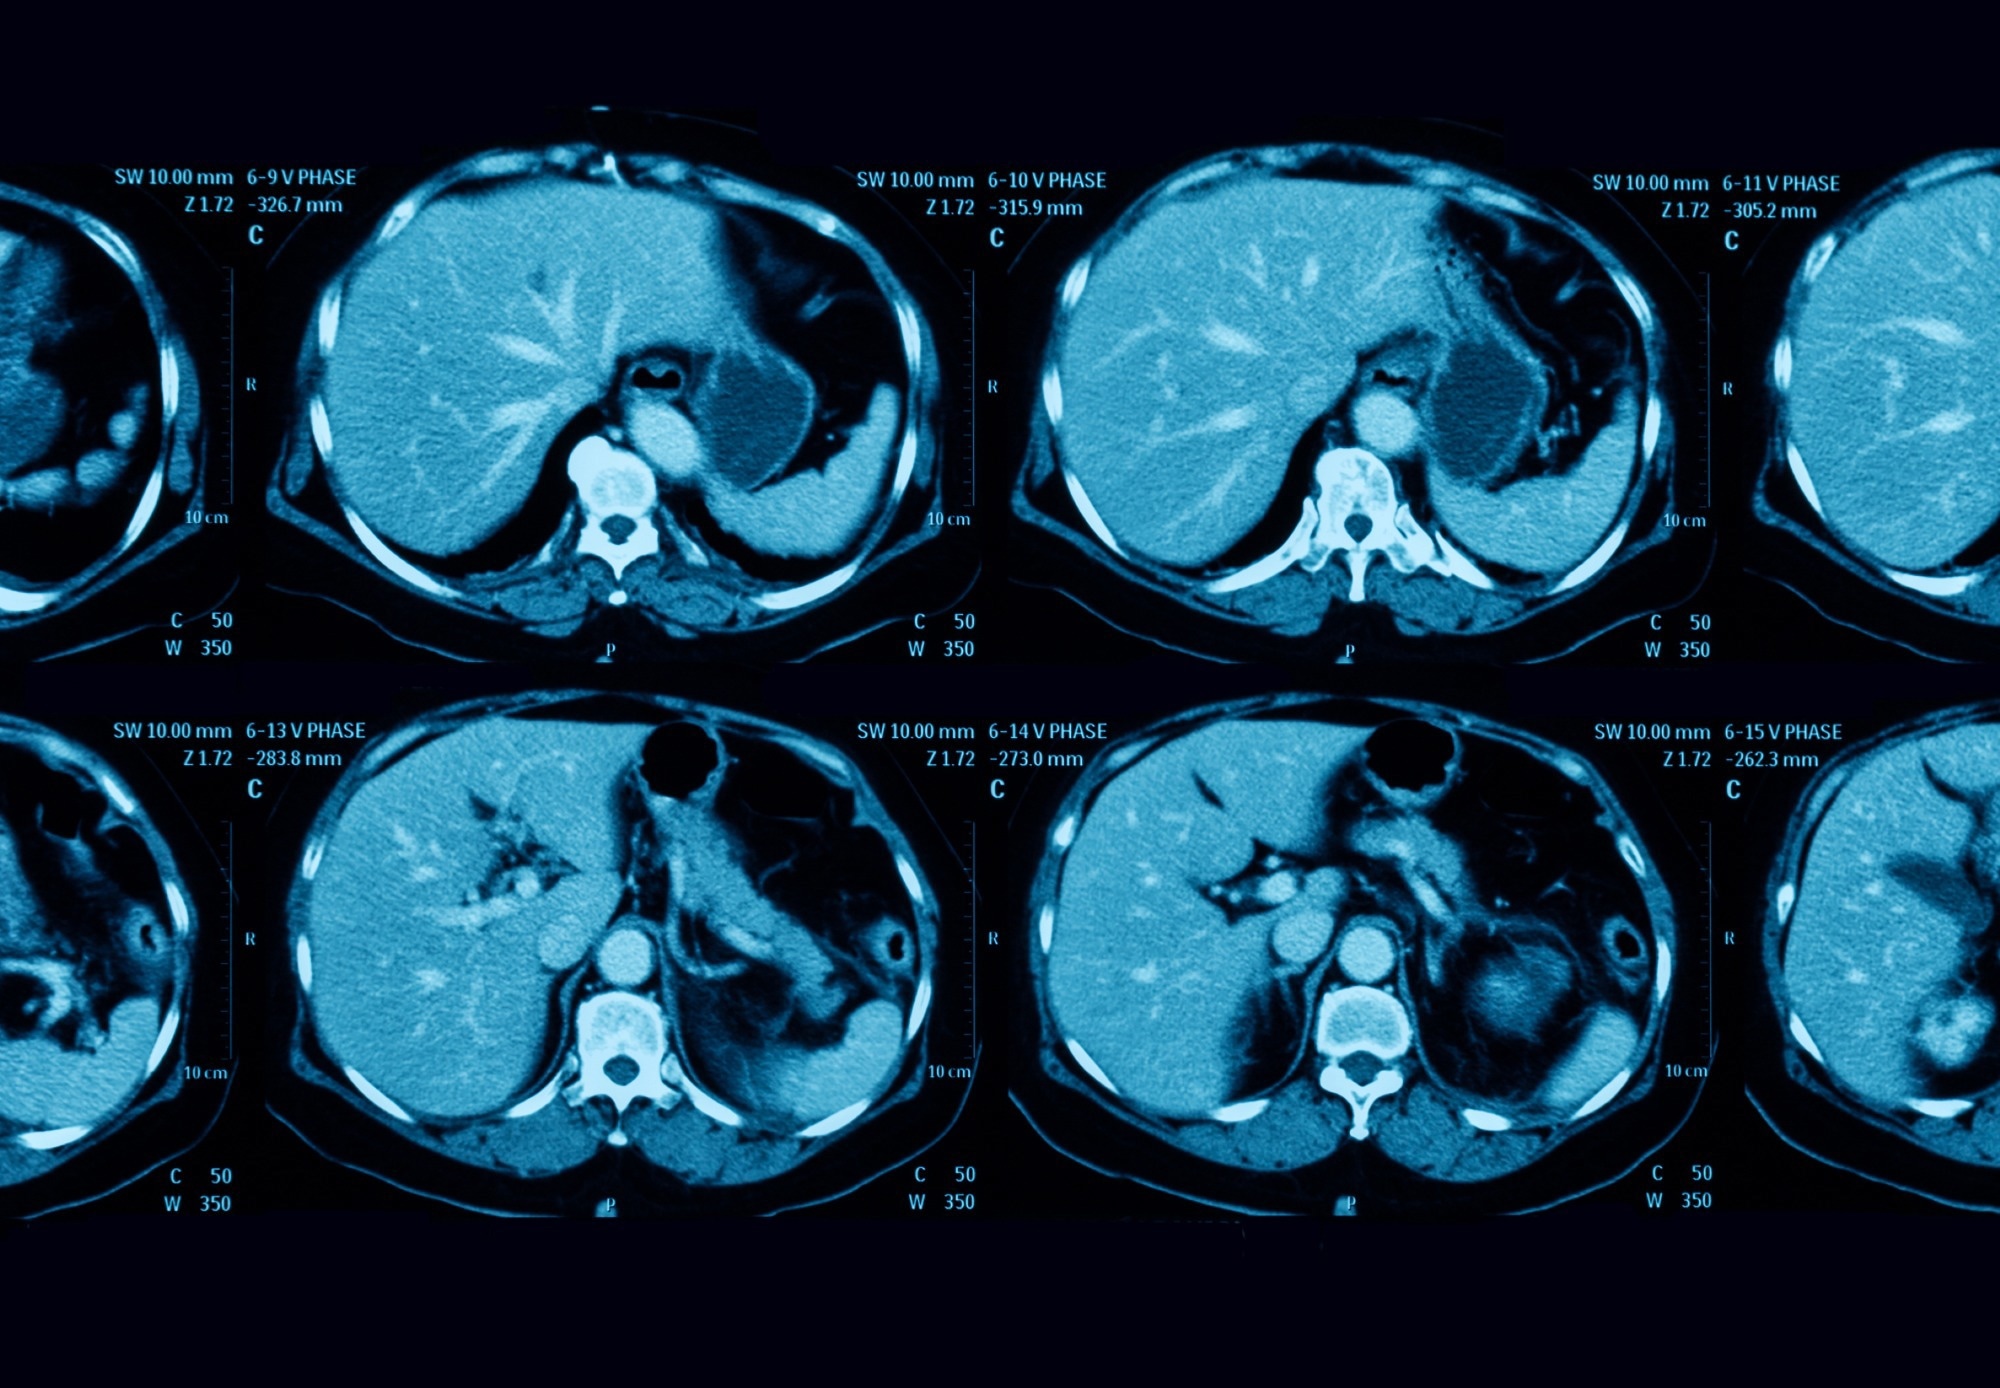

Study: Pancreatic Cancer Detection on CT Scans with Deep Learning: A Nationwide Population-based Study. Image Credit: Suttha Burawonk / ShutterstockStudy: Pancreatic Cancer Detection on CT Scans with Deep Learning: A Nationwide Population-based Study. Image Credit: Suttha Burawonk / Shutterstock

In the present study, researchers tested and validated a similar computer-aided detection (CAD) tool that harbored CNN for segmenting the pancreas on CT images. Additionally, this tool had an ensemble classifier with five independent classification CNNs to predict the presence of pancreatic cancer. They obtained all the CT scans analyzed in the portal venous phase, 70–80 seconds after intravenous administration of the contrast medium.